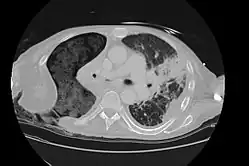

Axial thoracic CT scan of a person with an Eloesser flap. Courtesy of Radiopaedia.org. From the case https://radiopaedia.org/cases/11383